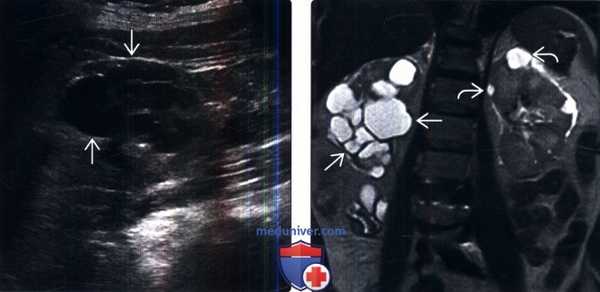

(Слева) УЗИ, продольная плоскость сканирования, правая почка: скопление множества кист. Каждая киста имеет типичный доброкачественный вид.

(Справа) МРТ, Т2-ВИ, коронарная проекция: у этою же пациента выявлено скопление кист в нижнем полюсе правой почки. Отсутствие капсулы позволяет предположить локализованную кистозную болезнь почек. Обратите внимание на рассеянные кисты левой почки.